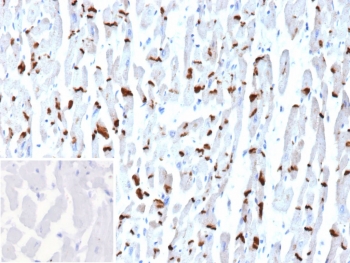

IHC staining of FFPE human heart tissue with Cadherin 2 antibody (clone CDH2/9494). Inset: PBS used in place of primary Ab (secondary Ab negative control). HIER: boil tissue sections in pH 9 10mM Tris with 1mM EDTA for 20 min and allow to cool before testing.